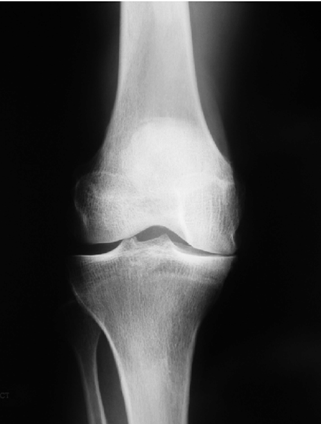

1. Knee Osteoarthritis and Orthotic Management

Unloader Knee Braces

One of the most effective non-surgical treatments for medial compartment knee osteoarthritis is the unloader knee brace.

Certified orthotists customize the brace according to limb alignment, thigh and calf measurements, and severity of deformity (varus or valgus knee).